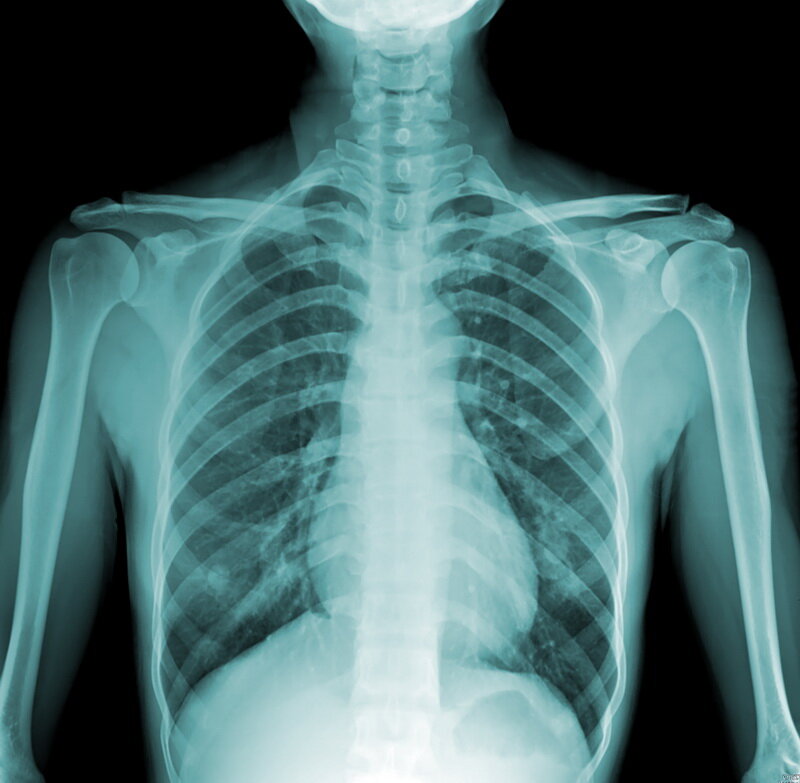

Правда ли, что легкие курильщика сильно отличаются от легких некурящего человека? На самом деле, курение, хоть и увеличивает риск развития заболеваний легких, но далеко не всегда так изменяет внешний вид самих органов. На самом деле на картинках с «легкими курильщика» показаны органы с запущенной стадией серьезных легочных заболеваний, при которых начинается некроз тканей. Но курение — далеко не единственная, а лишь одна из многих возможных, причин развития этих состояний. Сказать, какие легкие принадлежат некурящему человеку, а какие курильщику не всегда берутся даже патологоанатомы. У курящих людей в равной степени могут быть как пораженные заболеванием, так и совершенно нормальные на вид органы.

Ранее исследователи показали, что у людей c определенными мутациями риск развития легочных заболеваний ниже. Это значит, что если такие люди курят, то ХОБЛ у них появляется реже. Это объясняет, почему у некоторых курильщиков легкие на вид ничем не отличаются от органов